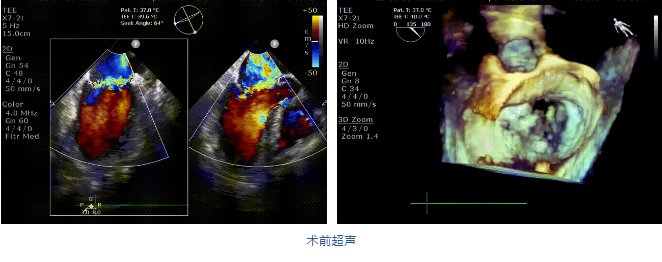

接受治療的是一例二尖瓣重度反流的患者,主訴“突發間歇性胸悶,氣急6天”。術前超聲提示:1.二尖瓣脫垂伴重度關閉不全(瞬時量30ml);2.左心、右房增大(左房容積110ml,左室容積129ml,右房容積55ml);3.左室收縮功能正常。患者在充分標準化藥物治療后(GDMT)仍然癥狀明顯,韓林教授及其團隊唐楊烽教授,以及心超科的周廣為醫生決定使用我國創新器械JensClip為患者進行二尖瓣緣對緣修復手術。

在阜外醫院潘湘斌教授團隊的支持下,手術經股靜脈-房間隔入路,采用全身麻醉插管,在TEE和DSA引導下完成房間隔穿刺。置入JensClip瓣膜夾系統后,在左房調整瓣膜夾的位置和軸向,后進入左室,在TEE引導下捕捉二尖瓣前后瓣葉,并關閉瓣膜夾。經TEE反復確認手術效果后最終鎖定并釋放瓣膜夾。術后即刻超聲顯示瓣膜夾位置穩定,功能良好,二尖瓣反流由術前4+減少至微量,手術圓滿成功。